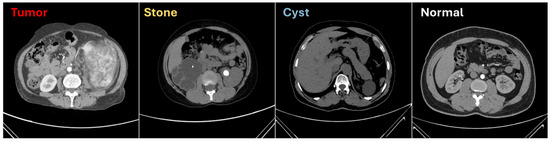

The datasets provided in Table 1 were utilized to evaluate the proposed model, DiagnosticMLP, comprising a wide range of medical CT scans. DICOM images from various hospitals in Dhaka, Bangladesh, formed the kidney CT dataset [51], which included four classes of kidney conditions, featuring a notably large number of images for cysts and normal kidneys. The abdomen CT dataset [52] comprised nine classes showcasing diverse abdominal issues, with the distribution of images ranging broadly across conditions, offering both common and rare cases. The chest CT dataset [53] was rich in images, particularly for bacterial pneumonia, and included conditions such as COVID-19, contributing to a dataset significant for training models in infectious disease diagnosis. Additionally, the kidney and chest cancer CT datasets [54] provided binary classifications between normal and cancerous conditions, with a substantial number of images that were key for the model to learn to discern cancer presence accurately. This ensemble of datasets, with their varied and ample images, was instrumental for developing the DiagnosticMLP model with an aim to automate and enhance the accuracy of medical diagnoses across a spectrum of conditions. Figure 2 presents exemplar images from the dataset employed to classify kidney CT scans into categories such as cysts, stones, tumors, and normal conditions [51].

Figure 2.

Sample from the computed tomography (CT) used for kidney conditions classification [51].